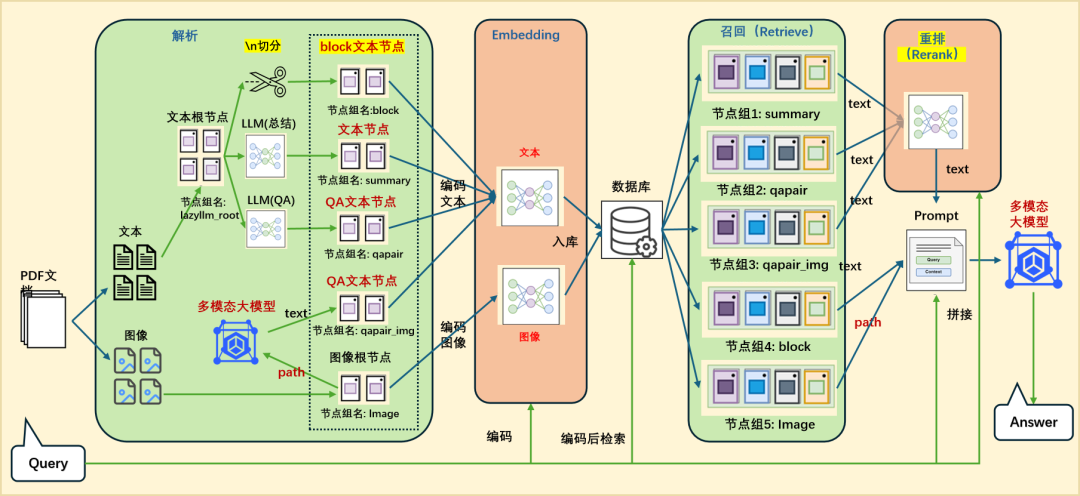

这部分我们聚焦在医学论文问答场景,结合文本+图像的多模态输入,构建一个更智能的 RAG 系统,并支持返回可视化图表。整体框架的细节如下:

首先,我们将PDF解析成文本和图像;文本部分我们可以通过\n切分、LLM(总结)和 LLM(QA)等方式构造不同的block文本节点;图像部分我们通过多模态大模型构建相应的QA文本节点qapair_img和图像根节点;接下来,我们将所有节点统一编码入库,并通过多路召回机制进行语义匹配与内容检索;在召回阶段之后,引入重排序机制,进一步优化检索结果的相关性与准确性;最后,系统会将用户的查询(query)与召回得到的上下文(context)内容一并输入至多模态大模型,由其生成最终答案。整体代码实现如下:

embed_mltimodal = lazyllm.TrainableModule("colqwen2-v0.1")embed_text = lazyllm.TrainableModule("bge-m3")embeds = {'vec1': embed_text, 'vec2': embed_mltimodal}qapair_llm = lazyllm.LLMParser(lazyllm.OnlineChatModule(stream=False), language="zh", task_type="qa")qapair_img_llm = lazyllm.LLMParser(lazyllm.OnlineChatModule(source="sensenova", model="SenseNova-V6-Turbo"), language="zh", task_type="qa_img") summary_llm = lazyllm.LLMParser(lazyllm.OnlineChatModule(stream=False), language="zh", task_type="summary") documents = lazyllm.Document(dataset_path=tmp_dir.rag_dir, embed=embeds, manager=False)documents.add_reader("*.pdf", MagicPDFReader)documents.create_node_group(name="block", transform=lambda s: s.split("\n") if s else '')documents.create_node_group(name="summary", transform=lambda d: summary_llm(d), trans_node=True)documents.create_node_group(name='qapair', transform=lambda d: qapair_llm(d), trans_node=True)documents.create_node_group(name='qapair_img', transform=lambda d: qapair_img_llm(d), trans_node=True, parent='Image')with lazyllm.pipeline() as ppl:with lazyllm.parallel().sum as ppl.mix:with lazyllm.pipeline() as ppl.mix.rank:with lazyllm.parallel().sum as ppl.mix.rank.short:ppl.mix.rank.short.retriever1 = lazyllm.Retriever(documents, group_name="summary", embed_keys=['vec1'], similarity="cosine", topk=4)ppl.mix.rank.short.retriever2 = lazyllm.Retriever(documents, group_name="qapair", embed_keys=['vec1'], similarity="cosine", topk=4)ppl.mix.rank.short.retriever3 = lazyllm.Retriever(documents, group_name="qapair_img", embed_keys=['vec1'], similarity="cosine", topk=4)ppl.mix.rank.reranker = lazyllm.Reranker("ModuleReranker", model="bge-reranker-large", topk=3) | bind(query=ppl.mix.rank.input)ppl.mix.retriever4 = lazyllm.Retriever(documents, group_name="block", embed_keys=['vec1'], similarity="cosine", topk=2)ppl.mix.retriever5 = lazyllm.Retriever(documents, group_name="Image", embed_keys=['vec2'], similarity="maxsim", topk=2)ppl.prompt = build_vlm_prompt | bind(_0, ppl.input)ppl.vlm = lazyllm.OnlineChatModule(source="sensenova", model="SenseNova-V6-Turbo").prompt(lazyllm.ChatPrompter(gen_prompt))lazyllm.WebModule(ppl, port=range(23468, 23470), static_paths=get_image_path()).start().wait()

🚨注意:由于在RAG中我们这里采用了多路召回,summary、qapair、qapair_img等节点组所在的路都会调用大模型,所以知识库越大的话,那么所消耗的时间和token都会很大,建议知识库中可以先用一两篇论文做尝试(论文中需要带图片)。